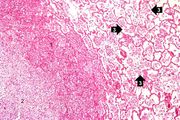

| 02:10, 19 August 2013 | IPLab3AcuteAppendicitis2.jpg (file) | 13 KB | Seung Park | This is a low-power photomicrograph of a normal appendix on the right and an appendix with acute inflammatory response on the left. Note the abundant blue-stained lymphoid tissue beneath the mucosal layer and the absence of blue-staining cells in the s... | 1 | |